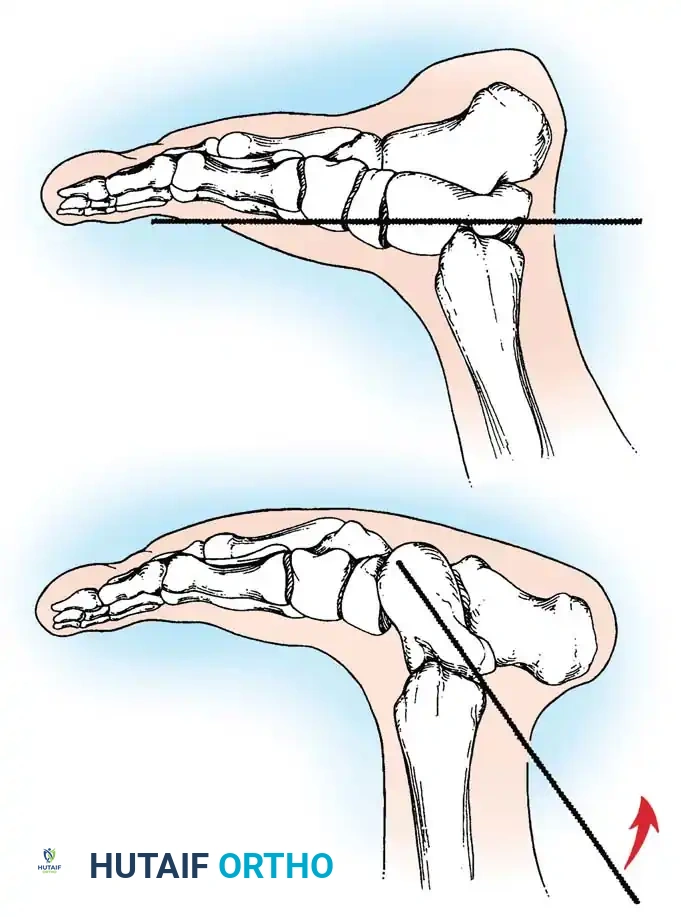

Differentiating CVT from severe but flexible pes planus or oblique talus requires rigorous radiographic evaluation. Standard weight-bearing (or simulated weight-bearing in infants) anteroposterior (AP) and lateral radiographs are required. However, the definitive diagnostic view is the plantar flexion lateral stress radiograph.

- Normal Foot / Flexible Pes Planus: On a plantar flexion lateral view, the long axis of the first metatarsal aligns with or passes plantarward to the long axis of the talus, indicating that the talonavicular joint is reducible.

- Congenital Vertical Talus: On the plantar flexion lateral view, the long axis of the first metatarsal remains rigidly dorsal to the long axis of the talus. This confirms the irreducible dorsal dislocation of the midfoot and forefoot on the hindfoot.

Surgical Warning: Failure to obtain a forced plantar flexion lateral radiograph can lead to misdiagnosis of an oblique talus as a true vertical talus, potentially resulting in unnecessary or overly aggressive surgical intervention.